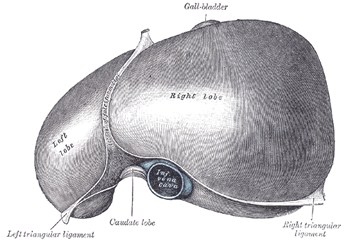

From the umbilicus,umbilical vein passescephalad, slightly toright

Joins the left branch ofthe portal vein

The ductus venosusarises from the pointwhere the UV joins theleft portal vein

Ductus venosus entersIVC

Tip inintrahepaticportal branch

Portal vein intosup. Mesentericvein